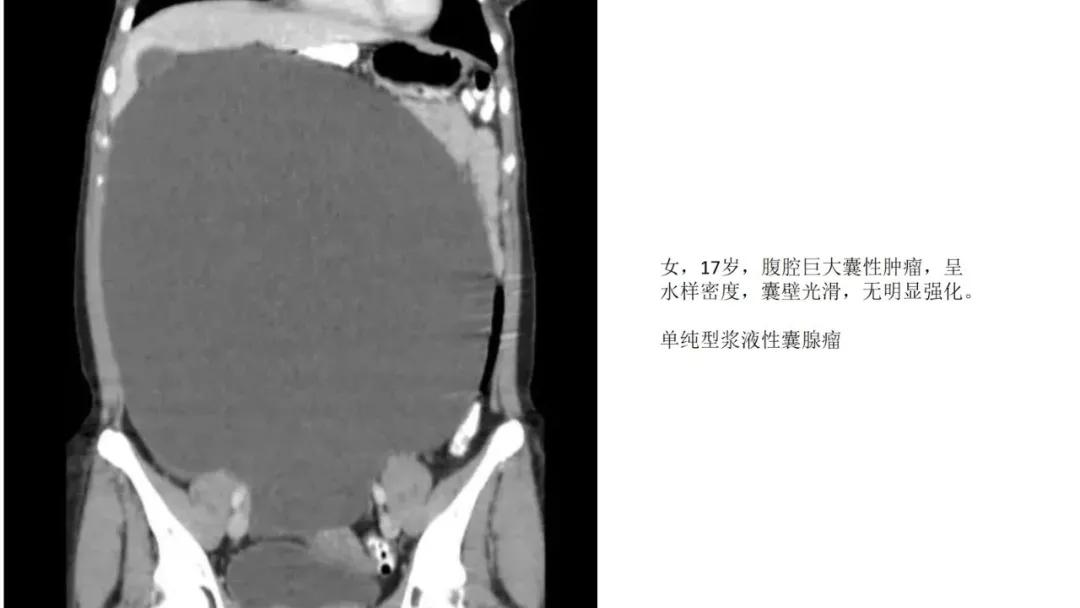

上皮性肿瘤:最常见,恶性多(卵巢癌),良性少。好发于50Y以上,发现时多为中晚期。多呈囊性或以囊性为主的囊实性肿块,完全实性者少见。形态多数不规则,边界模糊,囊壁及房间隔常不规则增厚,菜花样肿物或壁结节,囊实性区域分界不清,实性肿瘤常有不规则低密度或坏死区,可有边界模糊沙粒状或块状钙化,中-高度强化。良性者边界清晰,囊壁薄光整,无壁结节,实性部分呈无或轻度强化。

- 卵巢癌中最常见的是浆液性囊腺癌,约占1/3。